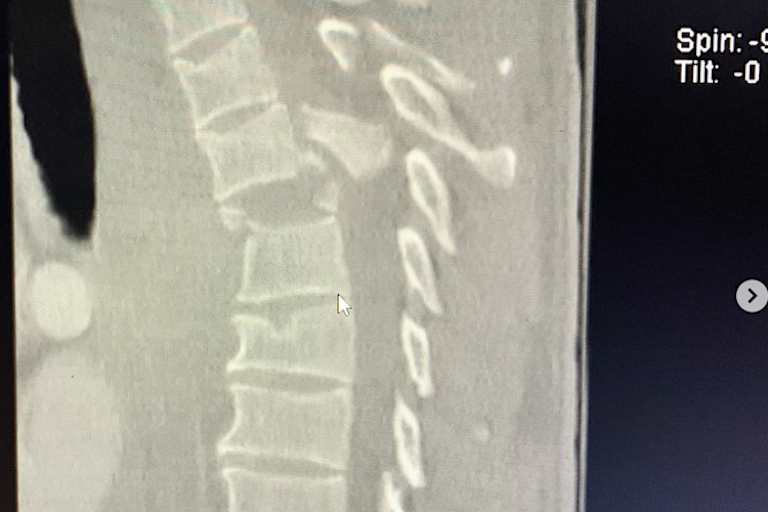

Trotz seiner waghalsigen Sprünge blieb er bis auf einige Schulterverletzungen während seiner langen Karriere von schweren Verletzungen verschont. Nun stürzte er ausgerechnet bei der Qualifikation für ein Amateur-Rennen der Senior 40+ Pro Klasse in Thunder Valley (Colorado), brach sich zwei Wirbel und zog sich eine Rückenmarksverletzung zu. "Ich werde von der Brust abwärts dauerhaft gelähmt bleiben", schrieb Matt aus dem Krankenhaus in Lakewood. "Die Operation diente der Stabilisierung meines Oberkörpers, damit ich aufrecht sitzen kann. Ich bin am Boden zerstört und bin mir nicht sicher, wie ich mein künftiges Leben gestalten soll. Hauptsächlich bin ich sauer, dass ich meine Familie in Probleme gebracht habe, nicht mit meinem Sohn Jett spielen kann und meine Frau Krystal in eine schwierigere Lage gebracht habe. Ich werde nur selbst aus der Situation herauskommen." Für Matt Buyten wurde auf der Plattform Road4Recovery ein Spendenkonto eingerichtet. Im Namen aller Leser von SPEEDWEEK.com wünschen wir von dieser Stelle aus viel Kraft und trotz der schwierigen Lage den notwendigen Optimismus für die Zukunft.